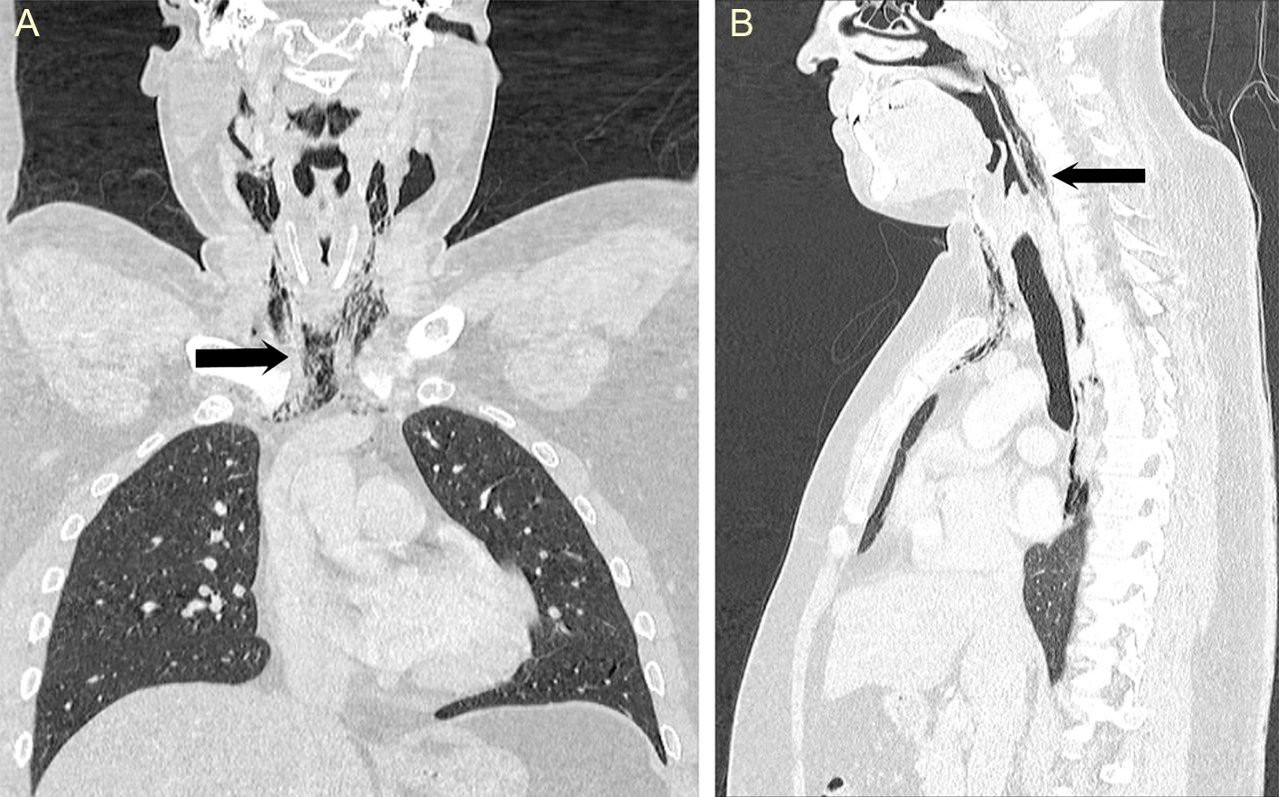

Các bác sĩ phải nhanh chóng tiến hành chữa trị bởi lỗ thủng cổ họng đã mở đường cho bong bóng khí tiến sâu vào các mô và cơ ngực của bệnh nhân, gây ra những âm thanh lụp bụp, răng rắc từ cổ xuống đến lồng ngực. Bên cạnh sự đau đớn, tổn thương còn mang đến nguy cơ khiến cho người đàn ông gặp phải nhiễm trùng vùng cổ sâu. Bệnh nhân sau đó đã được đặt ống truyền thức ăn và tiêm kháng sinh chống nhiễm trùng cho đến khi vết thương hết sưng và bớt đau. Thật may mắn chỉ khoảng một tuần điều trị, người này đã hồi phục sức khỏe và được về nhà với lời khuyên nhớ đời: Không bao giờ được nhịn hắt hơi nữa!

Các chuyên gia nhấn mạnh bạn cần phải tránh thói quen nhịn hắt hơi này vì nó gây nhiều nguy hiểm hơn chúng ta đã nghĩ. Nó có khả năng dẫn đến những biến chứng như pseudomediastinum (trường hợp không khí kẹt trong lồng ngực, giữa hai lá phổi), thủng màng nhĩ, thậm chí là vỡ mạch máu não. Ngoài ra vệc xì mũi quá mạnh cũng có thể gây ra hậu quả tương tự. Vây nên mỗi khi muốn hắt xì hơi, thay vì cố bịt mũi nhịn, bạn hãy quay mặt vào trong tường hoặc che miệng lại để tránh việc mất vệ sinh, ảnh hưởng đến những người xung quanh nhé!